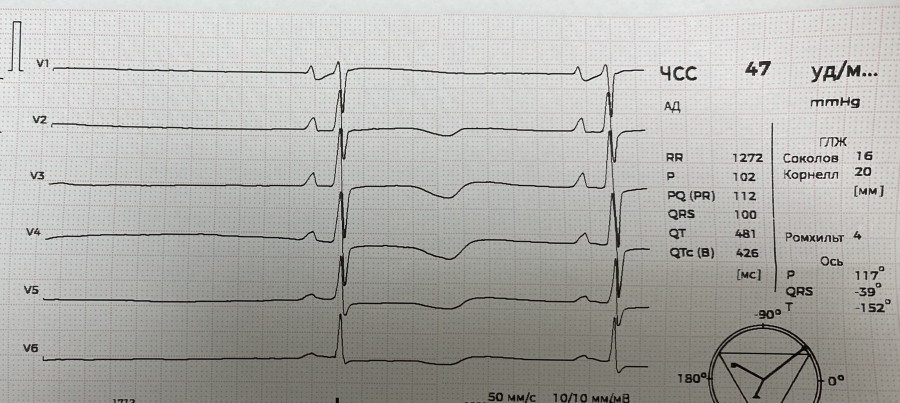

СА блокада

IMG_8979.JPG

IMG_8979.JPG [ 1.46 MiB | Просмотров: 706 ]

IMG_8980.JPG

IMG_8980.JPG [ 1013.55 KiB | Просмотров: 706 ]